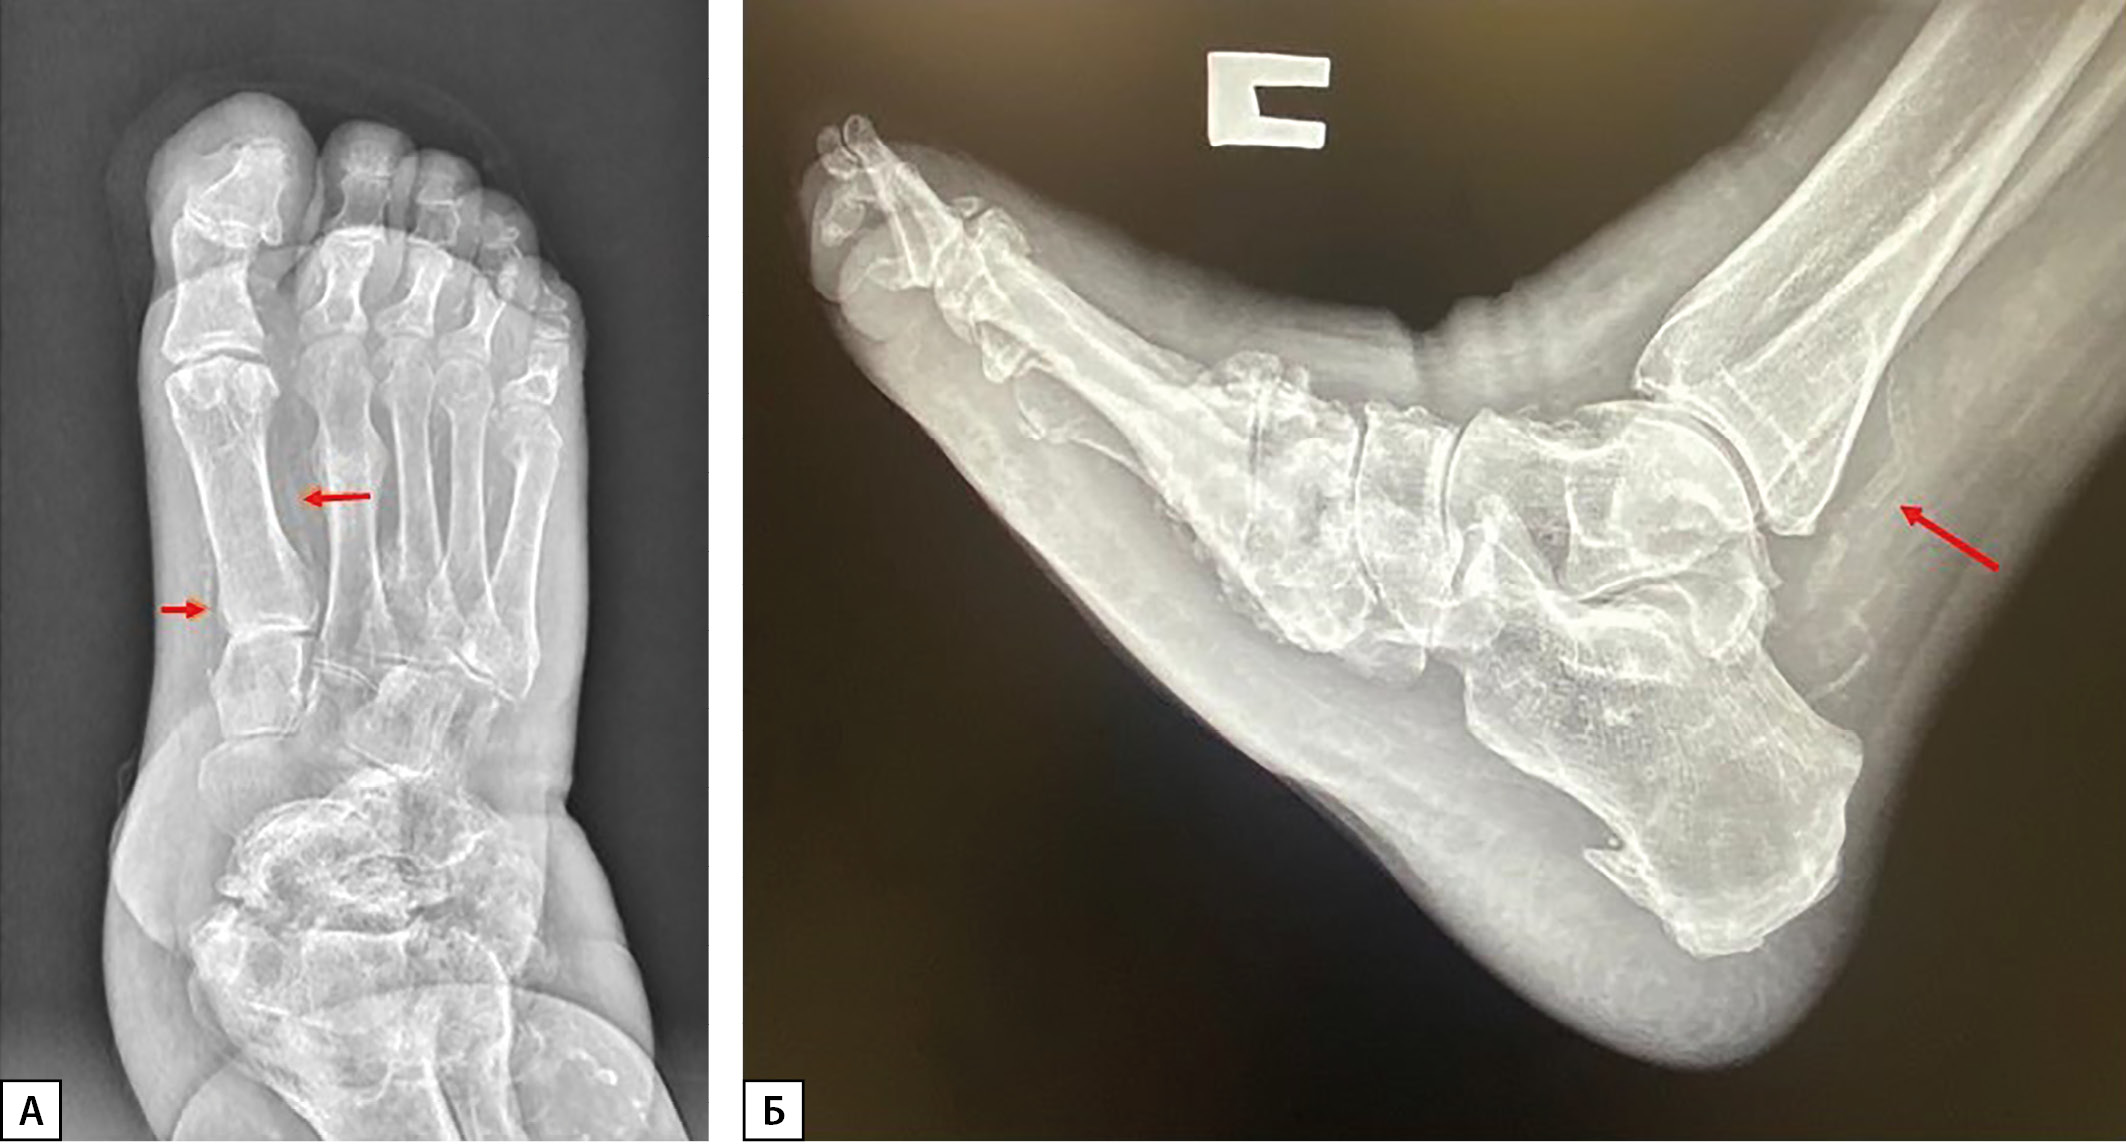

Метаболические и структурные изменения в костной ткани при ДНОАП сопряжены с медиакальцинозом (МК) артерий нижних конечностей вследствие ДН, одного из наиболее распространенных осложнений СД. У пациентов со стопой Шарко наблюдается локальный остеопороз стоп, и в 90% случаев происходит обызвествление сосудов стоп и голеней (рис. 1 А, Б) [3] . Выявляемый рентгенологически МК артерий нижних конечностей нередко ошибочно принимают за облитерирующий атеросклероз, что приводит к неверной тактике лечения. Обызвествление стенок артерий может обнаруживаться и у лиц без нарушений углеводного обмена, причем с возрастом частота МК возрастает (от 5% у молодых до 37% у пожилых). При СД МК выявляется в среднем в 3 раза чаще, чем у лиц с нормальным углеводным обменом [6]. По данным ряда исследований, распространенность МК была выявлена у 17–42% пациентов с СД 2 типа (СД2) [7], у 27–40% пациентов с прогрессирующей ХБП [8].

Рисунок 1. А. Рентгенограмма левой стопы пациента с ДНОАП в прямой проекции.

(стрелками обозначен медиакальциноз артерий стопы).

Б. Рентгенограмма правой стопы пациента с ДНОАП в боковой проекции